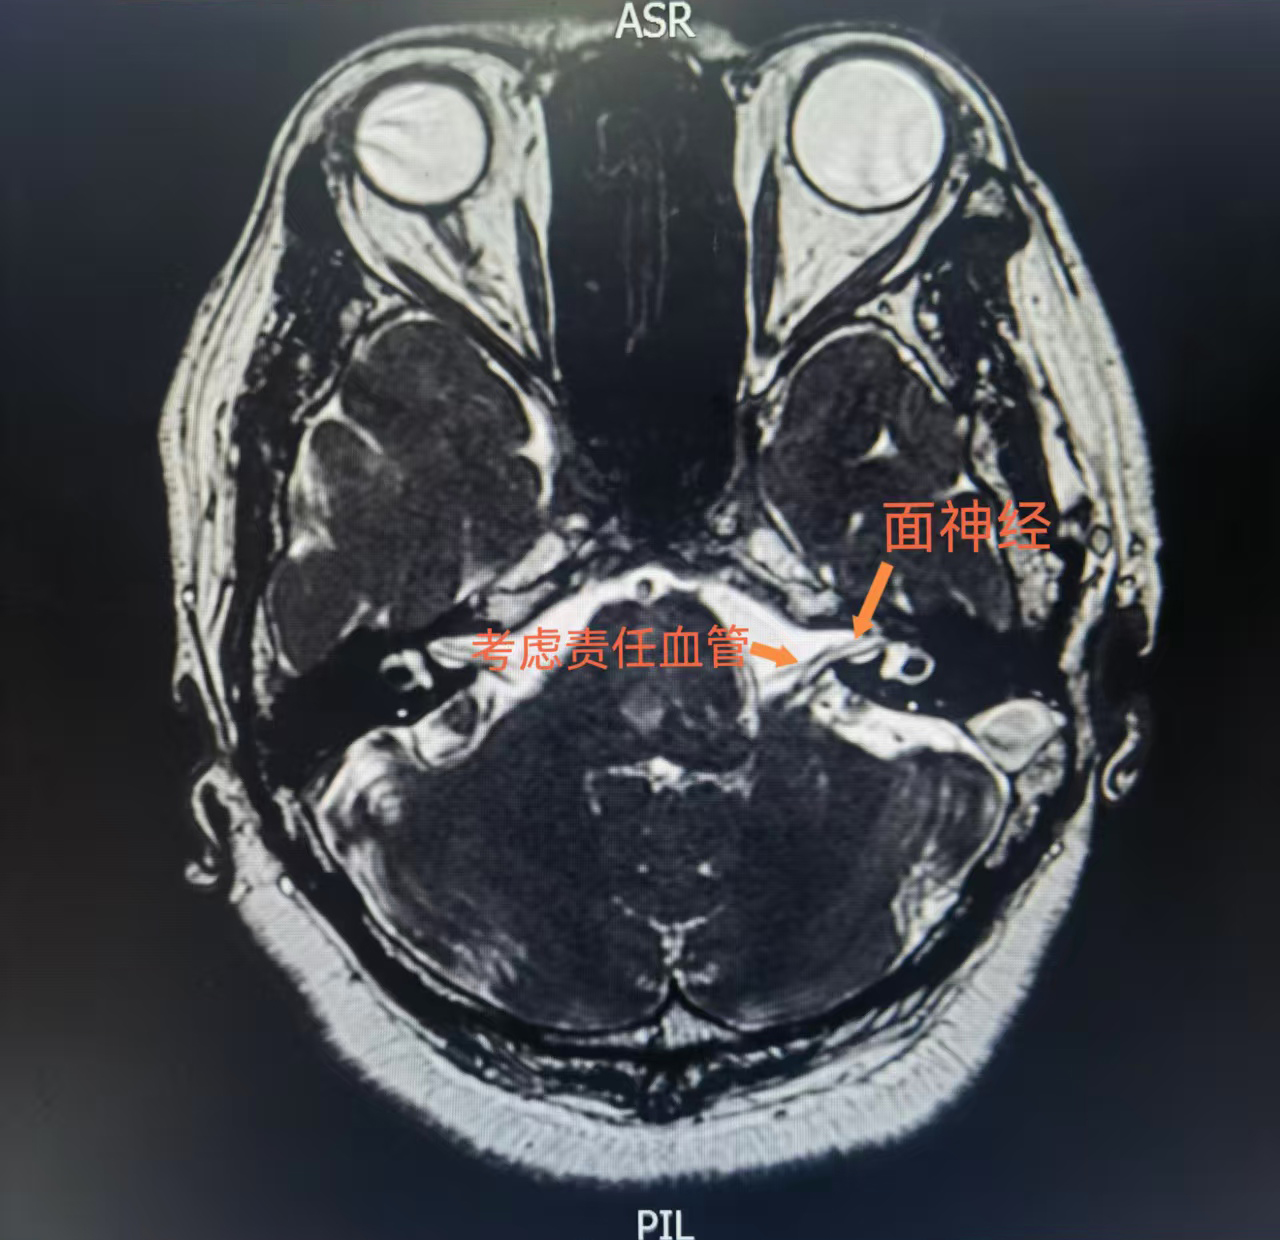

近日,仙桃市第一人民医院神经外科团队在华中科技大学同济医学院附属同济医院神经调控中心主任、仙桃一医副院长蒋伟教授的指导下,成功为一位饱受面肌痉挛困扰8年的患者实施了面神经微血管减压术,精准解除了患者左侧面部反复抽搐的症状。医院在功能性颅神经疾病外科诊疗领域实现了新的技术突破。

蒋伟教授带领仙桃一医神经外科团队对肖女士的病情进行了系统评估。尽管患者年龄偏大并伴有高血压,但综合判断其保守治疗效果不佳,且无绝对手术禁忌,具有明确的手术指征。团队经充分讨论,最终确定了创伤小、效果确切的“面神经微血管减压术”作为治疗方案,并制定了周密的手术预案。

手术由仙桃一医神经外科孙道法副主任医师主刀,在蒋伟教授的全程指导与神经电生理监测护航下顺利实施,全程历时3小时,期间患者生命体征一直保持平稳。